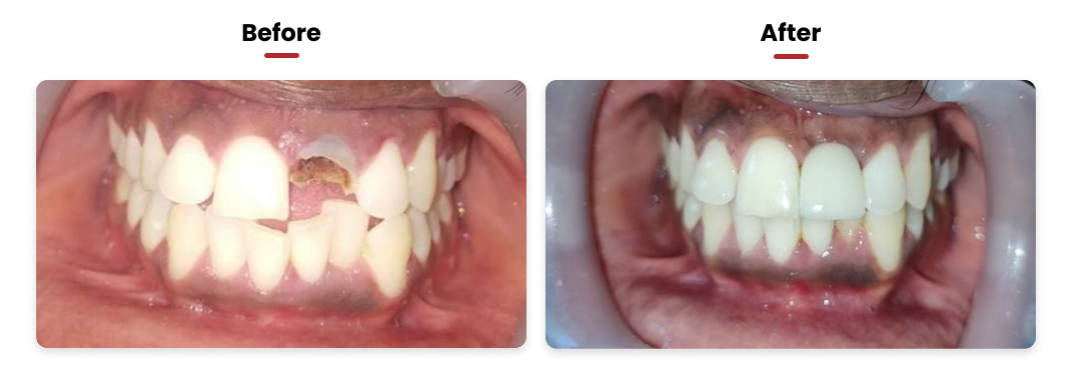

• When multiple teeth are absent, it can significantly hinder the ability to chew food effectively. In such situations, the placement of more than one dental implant becomes necessary. These implants serve as the foundation for an implantsupported bridge, onto which crowns are attached. Patients have the option to select materials like Porcelain Fused to Metal (PFM) or zirconia for these crowns.

• This technique stands out as the optimal method for replacing natural teeth. It notably enhances the aesthetic appeal of one’s smile, particularly in areas where new teeth are visible. As a result, it boosts confidence in smiling and speaking.

• Another significant advantage of this approach is its role in bone preservation. It contributes to improved periodontal health, leading to healthier gums and overall enhanced oral health compared to the state with missing or loose teeth